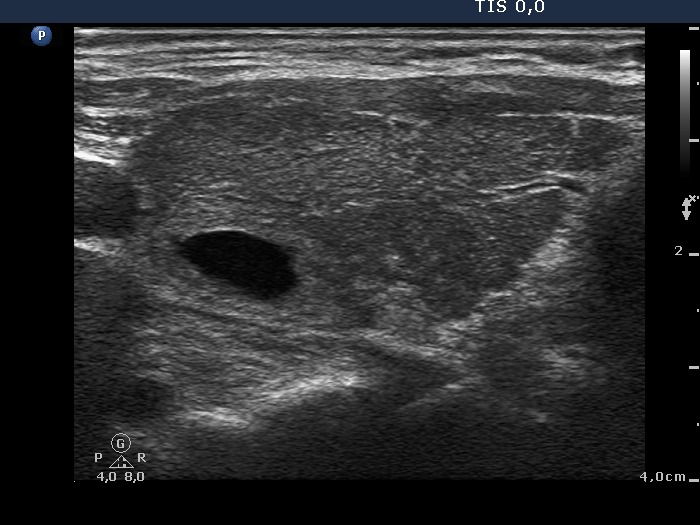

Graves' disease - Case 36 (ultrasonographic picture 5)

Left lobe, longitudinal scan. There is a hyperechogenic cystic nodule in the upper-dorsal part of the lobe while a hypoechogenic area right to the nodule.